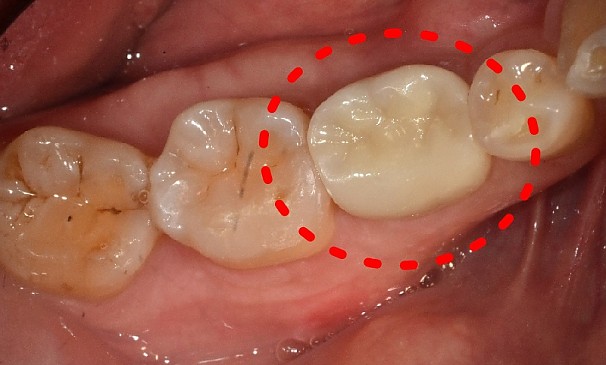

이OO님 전후사진 | 치료 기간 : 1주

치료 전

치료 후

치아머리확보술